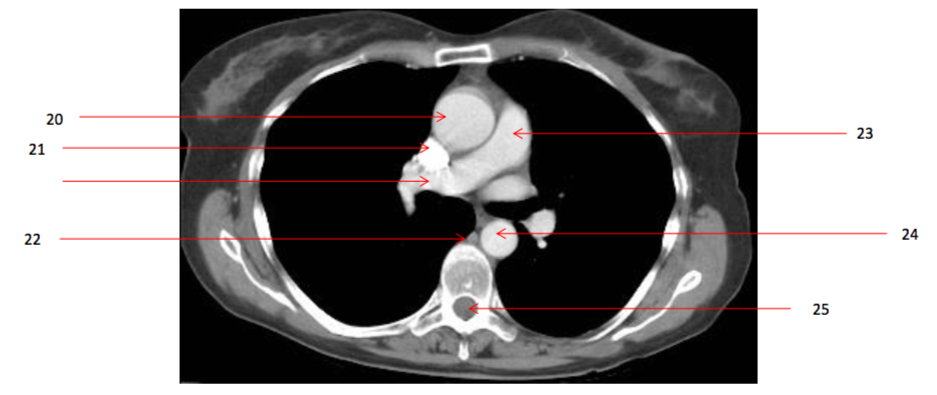

12

Number 23?

Pulmonary trunk

16

Number 17?

SVC

18

Number 20?

Ascending aorta

Q

Number 21?

23

Number 22?

24

Number 29?

Azygos vein

26

Number 27?

29

Number 44?

R atrium

30

Number 28?

Rt pulmonary vein

32

Number 24?

Descending thoracic aorta